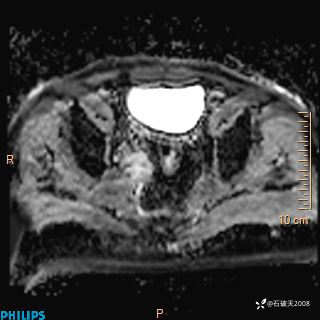

2023年3月份MRI影像

增强轴位